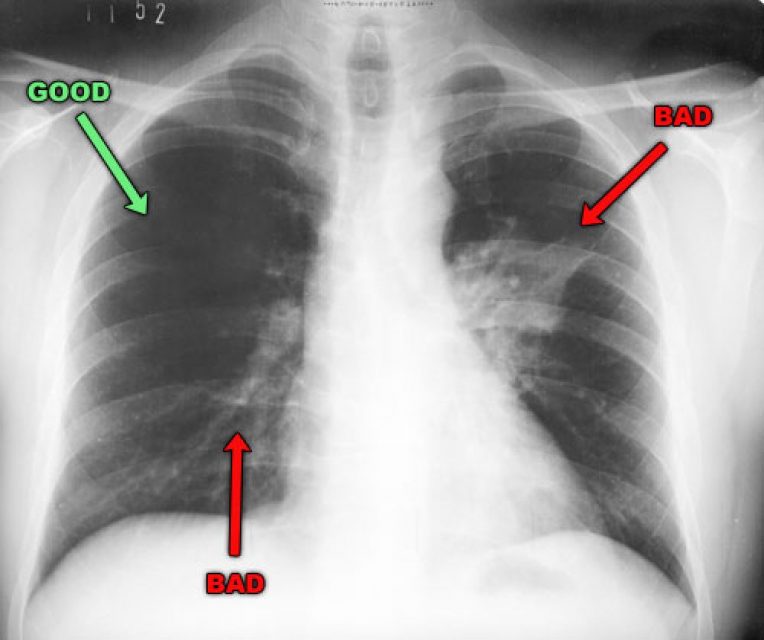

Обычно при туберкулезе аускультативные данные являются довольно скудными, но при этом на рентгене видны достаточно обширные поражения легких. При пневмонии аускультативные признаки могут быть очень разнообразными, но изменения тканей являются умеренными. Сделать ретген вы можете в нашей клинике, а если вас интересуют цены на УЗИ, ищите их на сайте.

Есть так называемое «золотое правило», помогающее отличить туберкулез и пневмонию, которое было известно еще в начала ХХ века: при туберкулезе характерны скудные аускультативные данные, которые сочетаются с обширным поражением легких, видимым при рентгеновской диагностике. При воспалении легких и умеренных изменениях ткани, видимых на рентгене, аускультативная картина очень разнообразна – хрипы, крепитация.

Есть так называемое золотое правило, помогающее различить туберкулёз и пневмонию, которое было известно ещё в начала ХХ века: при туберкулёзе характерны скудные аускультативные данные, которые сочетаются с обширным поражением лёгких, видимым при рентгеновской диагностике. При воспалении лёгких и умеренных изменениях ткани, видимых на рентгене, аускультативная картина очень разнообразна – хрипы, крепитация.